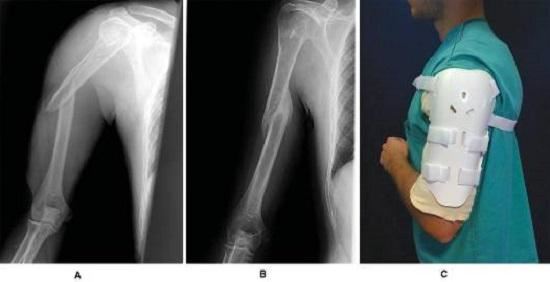

1、治疗手段。骨折后的保守治疗,通常是指手法复位后再使用支具固定,让断骨自行修复的一种治疗手段。保守治疗过程不会产生新的创口,但由于手法复位和支具固定的局限性,可能会出现对线不精准、移位大、骨骼愈合慢等问题。2、适应证。保守治疗大多用于无明显移位或稳定性骨折(例如:外展型、嵌入型的,且不涉及重要神经血管损伤的骨折),另外,对于年龄较大、健康状况差、不能耐受手术、难以配合术后康复训练者,也尽可能采用保守治疗。